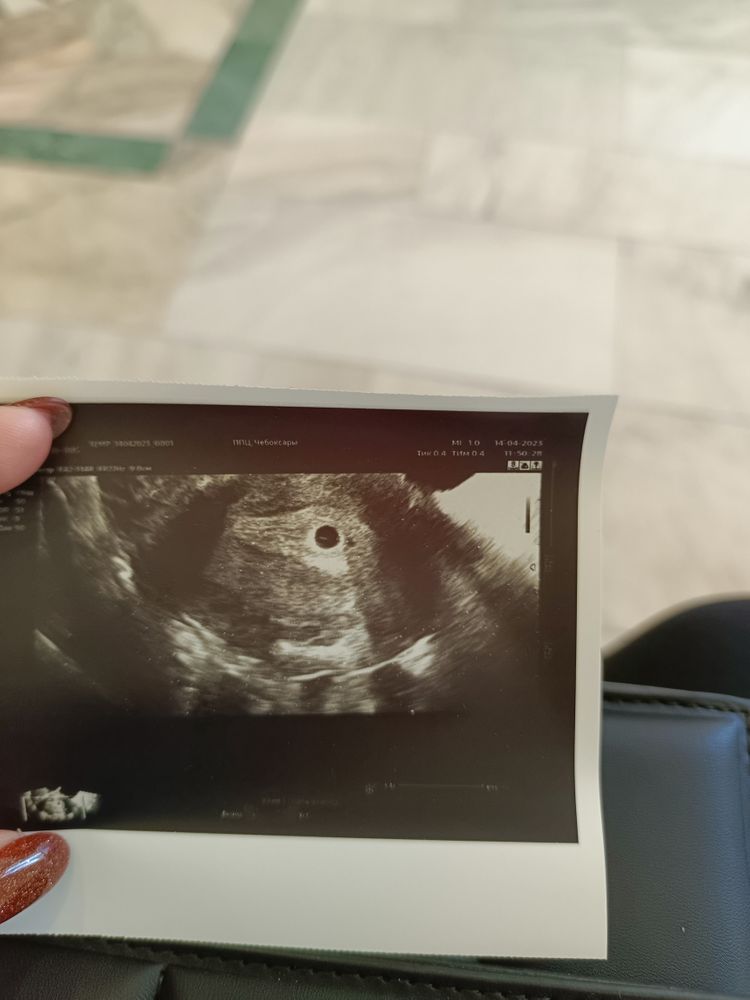

Нет эмбриона, размеры жм

А пока есть вопросы по желточному мешочку, как думаете, нормальная динамика? 14.04 1,8мм - 23.04 4,1мм

Мне кажется, что при таком жм видно эмбрион... Фото от 14.04